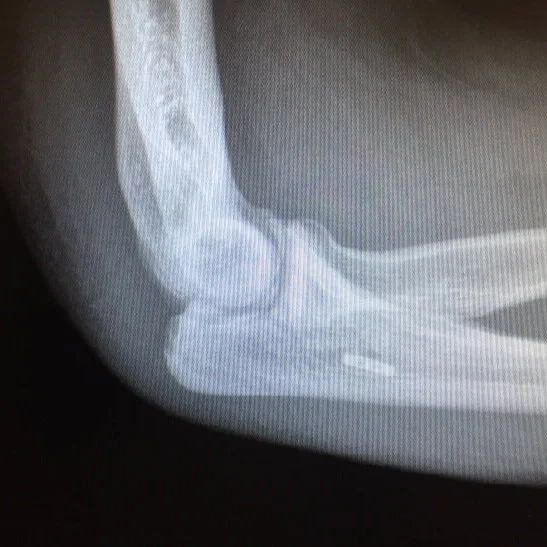

“I have been using the Elbow LOC arm holder for the past several years. It is extremely helpful for my elbow ORIF cases to securely maintain the elbow in position while the patient can remain supine and the entire device is sterile and in the field without needing to be covered with another sterile device.”